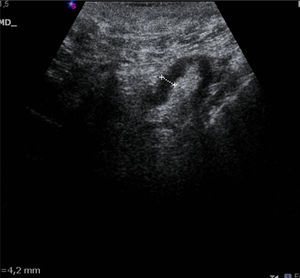

The US parameters evaluated were: cortical thickness, morphological changes in the hilar fat and characteristics of the cortical vascular flow. The following were considered findings suspicious for metastasis: local or diffuse cortical thickness ≥3mm (Fig. 1), absence, obliteration or eccentric location of the hilar fat (Fig. 2), and/or non-hilar cortical vascular flow (NHCVF) (Fig. 3) on color Doppler-duplex US with parameters set for low velocity flow detection (pulse-repetition frequency at 488, velocity scale at 3cm/s), and individualized setting for the rest of parameters. CNB was performed in those lymph nodes showing one or more of these parameters. When several lymph nodes showed US abnormalities, the most suspicious node was sampled, considered as the one with the largest number of parameters indicative of metastasis. At an equal number of parameters, the absence of hilar fat was the prevailing criterion in the selection of the lymph node, since this is the parameter with the highest positive predictive value (PPV) described in the literature.12,21,22 None of the patients in our series had several suspicious lymph nodes with one single US finding different in each lymph node. Access to the lesions was not a limitation for CNB in any of the patients.

Cortical thickness >3mm was found in 21 (78%) of the 27 patients with negative CNB; morphological changes in the hilar fat were found in 2 patients (7%), and NHCVF in 8 patients (30%), with 2 or more US criteria of metastasis found in several lymph nodes. Of the 50 patients with positive lymph nodes (positive CNB or negative CNB with positive sentinel node), cortical thickness was found in 44/50 patients (88%), changes in the hilar fat in 20/50 patients (40%) and NHCVF in 29/50 patients (58%). Considered individually, the absence or obliteration of the hilar fat was the US parameter with the highest PPV (90%) against NHCVF (78%) and cortical thickening (68%). The combination “cortical thickening and NHCVF” was positive in all cases detected in our series (100% PPV) (Table 1).

US is the most widely used technique in the preoperative evaluation of axillary lymph nodes, with a wide range of sensitivity (35%-95%) related to the experience of the operator and the variety of parameters considered as possible predictors of metastatic disease.17,18,24–26 The absence of hilar fat is considered an US parameter with high PPV and low sensitivity.12,21,22 This is in line with the results obtained in the present study: this was the least common finding (40%), with a PPV of 90%.

The most common US finding was cortical thickness >3mm, with a PPV of 68% and a sensitivity of 88%, slightly below the results obtained by Deurloo et al.17 and Abe et al.12 in their series; although Deurloo et al. considered a cortical thickness of at least 2.3mm. In their study, Abe et al.12 reported an excessively low sensitivity for this parameter (6%) and propose as possible indicator “the ratio between the cortical thickness and the short axis of the lymph node”, against cortical thickening alone.